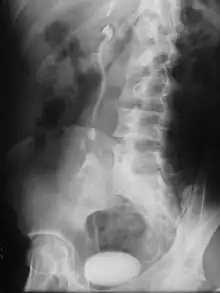

Radiographie montant une ectopie rénale.

- (Anatomie) Position anormale d'un organe.